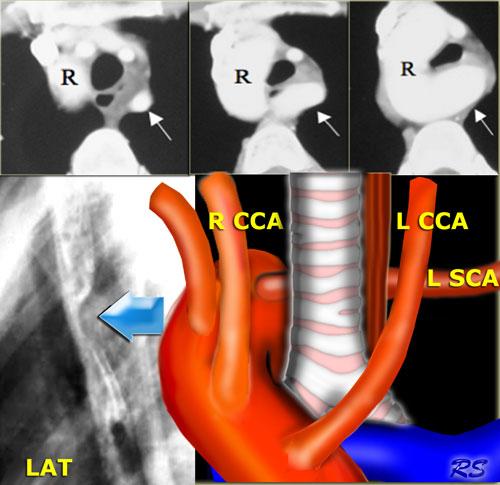

Quai động mạch chủ phải kèm động mạch dưới đòn trái bất thường

Quai động mạch chủ phải kèm động mạch dưới đòn trái bất thường thường là phát hiện tình cờ.

Tuy nhiên, quai động mạch chủ phải với phân nhánh đối xứng (mirror-image branching) hầu như luôn đi kèm với bệnh tim bẩm sinh.

CT cho thấy quai động mạch chủ phải (R) và động mạch dưới đòn trái bất thường (mũi tên) xuất phát thấp từ quai và chạy sang trái phía sau thực quản và khí quản.

Bên trái là hình chụp thực quản cản quang của bệnh nhân có quai động mạch chủ phải tạo ra ấn lõm phía sau trên hình chiếu nghiêng (mũi tên xanh dương).

Sơ đồ minh họa động mạch dưới đòn trái bất thường (L SCA) nằm phía sau khí quản và thực quản.